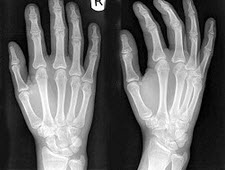

46、单项选择题

女,25岁,腕部疼痛,结合图像,最可能的诊断是()

218、单项选择题

女,根据其正常手的影像图像,判断其最可能的年龄()

223、单项选择题

女,50岁,手指关节肿痛,晨僵,结合图像,最可能诊断是()